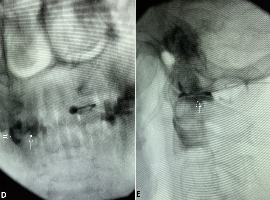

Citation: Yakov Perper, et al. Rare Examples of the Space of Okada Spread. Clin Image Case Rep J. 2021; 3(3): 146.